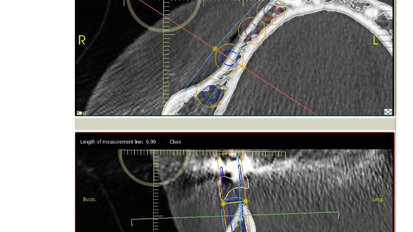

Nový úsměv za jeden den

Čt. 28. května 2020